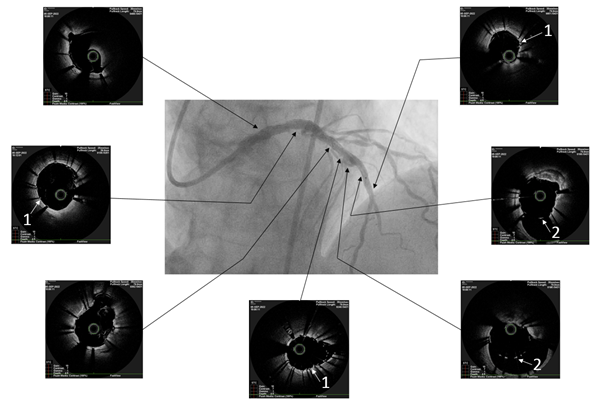

The patient underwent endovascular rotational atherectomy followed by stenting of the affected segments of the coronary arteries. The intervention was carried out under the control of optical coherence tomography (OCT). Initially, the right common femoral artery was punctured under local anesthesia and a 7F introducer was placed. Next, the guide catheter was placed at the mouth of the LCA. The coronarogram revealed 80% calcified stenosis in the terminal LCA OS with a transition to the proximal segment of the LAD and 90% calcified stenosis in the middle segment of the LAD (Figure 1). Using a microcatheter, a conductor was introduced into the apical segment of the LAD. Next, the destruction of calcified atherosclerotic plaques in the LCA and LAD was performed using the Rotablator system of rotational atherectomy (Figure 2), after which, under OCT control (Figure 3), predilatation of the stenotic areas of the LAD with a 2.25x15 mm balloon catheter was performed, followed by positioning and implantation in the area of residual stenoses in the middle segment of the LAD, the proximal segment of the LAD and the OS of the LCA of everolimus drug-eluting stents 3x38 mm and 4x38 mm, respectively. Then, post-dilatation of the stented segments with 3.5x20 mm, 4.5x15 mm balloon catheters and proximal optimization in the LCA OS with a 5x15 mm balloon catheter were performed, achieving a good angiographic result: blood flow in the TIMI-3 arteries. On the control image and OCT control, the stents were fully extended, no signs of dissection were detected, and no residual stenoses were found (Figure 4, 5).

Figure 4 Angiographic result of balloon angioplasty and stenting.

Figure 5 Optical coherence tomography after balloon angioplasty and stenting.

White arrows indicate full adherence of stent cells to the vessel wall (acoustic shadows of stent strata) (1) and stent cells in the area of aneurysmal expansion of the vessel (2).